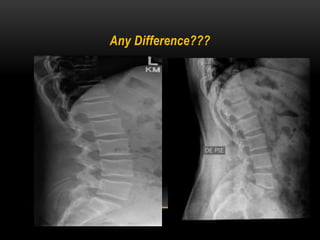

Any Difference???

FLEXION AND EXTENSION VIEWS